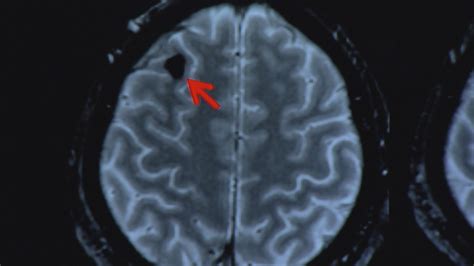

When a doctor reviews a CT scan for concussion, they are looking specifically for evidence of high-risk injuries. A negative scan—meaning the scan shows no injury—is excellent news. It means the patient does not have an acute bleed or fracture requiring surgery. However, a negative scan does not rule out the diagnosis of a concussion. The concussion diagnosis is based on the patient's symptoms and clinical assessment rather than imaging.

If the scan comes back positive, it indicates a more serious traumatic brain injury. This may require admission to the hospital, observation in an Intensive Care Unit (ICU), or, in rare cases, neurosurgical intervention to relieve pressure on the brain. Early detection through imaging is the key to preventing secondary brain damage.